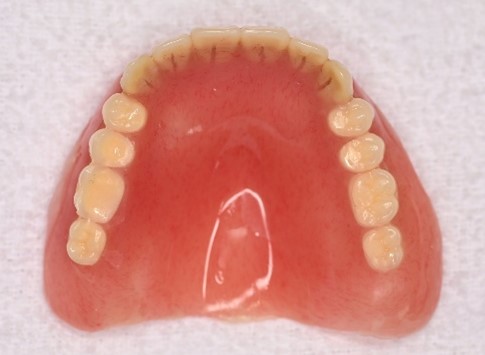

女性Sさん 70代(マグネット式入れ歯)

主訴

右の前歯がぐらぐらする。

治療内容

右前歯は残すことができず、抜歯しました。上顎残り5本の歯のうち4本を利用しマグネット義歯を装着しました。

所感

マグネット義歯は、非常に安定がいい義歯です。残っている歯が少なくなってきた時には、それらの歯を効果的に利用することができるとても良い方法だと考えます。口蓋隆起がありましたので、それを避けて馬蹄形のかたちの義歯にしました。マグネット義歯の場合、これが可能になります。通常の総義歯であると、この形にしますと安定が悪くなりますので出来ません。